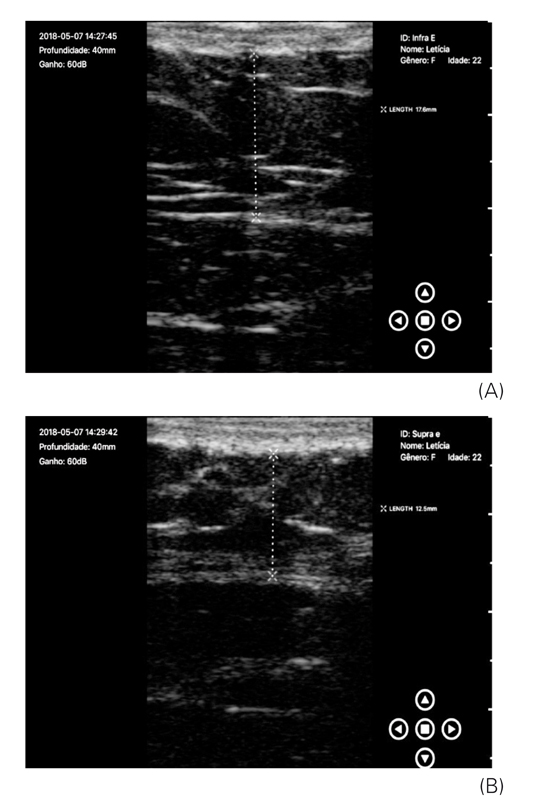

Verificou-se que, no momento inicial nas avaliações das medidas supra e infraumbilical, já existia uma diferença, fato que dificultou a interpretação dos resultados na avaliação final, quando também se observou uma diferença entre as zonas supra e infraumbilical esquerda. Mas ao analisar as imagens de ultrassonografia individualmente, é possível perceber a diferença entre as regiões tratadas e controle, conforme demonstra as Figuras 3A e 3B (análises ultrassonográficas da região infra e supraumbilical esquerda antes do tratamento), Figuras 4A e 4B (análises ultrassonográficas da região infra e supraumbilical direita, controle), Figuras 5A e 5B (análises ultrassonográficas da região infra e supraumbilical esquerda após tratamento) e Figuras 6A e 6B (análises ultrassonográficas da região infra e supraumbilical direita após tratamento, controle).

(A) Análise ultrassonográfica da região infraumbilical esquerda, após tratamento, 1,76 cm; (B) Análise ultrassonográfica da região supraumbilical esquerda, após tratamento, 1,25 cm

Os autores.

Por meio das imagens de ultrassonografia demonstradas nas Figuras 3 e 5 e dos dados contidos na Tabela 2, verificou-se que a região tratada teve uma redução importante, comparada com a do lado controle, de 0,6 cm na região infraumbilical e 0,15 cm na região supraumbilical. Do total da amostra, 21 mulheres apresentaram esse comportamento, assim a diferença sempre foi mais acentuada na região infraumbilical, na qual o aplicador da TOC foi utilizado de forma estacionária. Mas no lado controle, percebeu-se que a região infraumbilical não se alterou após o período de quatro semanas e na região supraumbilical a redução foi 0,14 cm, em uma voluntária. Em seis participantes, a região supraumbilical não apresentou redução. Não foram feitas análises em quatro mulheres, pois estas não realizaram o exame final. A análise foi feita pela avaliação do ultrassonografista.